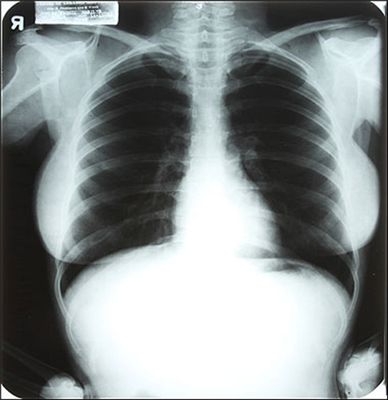

마릴린 먼로 가슴 X선으로 찍어보니..

(사진=줄리언스 옥션스)

[아시아경제 이진수 기자] 20세기 섹시 아이콘 마릴린 먼로(1926~1962)의 가슴을 X선으로 촬영한 사진이 오는 6월 경매에 붙여질 예정이다.영국 타블로이드 신문 더 선은 오는 6월 26~27일(현지시간) 경매에 나올 먼로의 개인 소장품들 가운데 한 점이 X선 사진이라고 12일 보도했다.‘MM’이라는 먼로의 이니셜이 새겨진 목재 스키 한 벌도 경매에 나온다. 예상 낙찰가는 800달러(약 90만 원).먼로가 말년에 사용한 초록색 벨벳 천을 씌운 의자는 4000달러에서 낙찰될 것으로 보인다. 이는 1962년 7월 ‘라이프 매거진’ 촬영 당시 사용된 것이다.먼로의 X선 흉부 사진은 1954년 플로리다주에 있는 시더스 오브 레바논 병원에서 찍은 것으로 예상 낙찰가는 1200달러.개봉도 하지 않은 샤넬 5 향수는 1200달러에 낙찰될 듯.먼로의 미완작 영화 ‘섬싱스 갓 투 기브’ 대본에는 개인 메모가 가득하다. 이는 8000달러에 팔릴 듯하다.푸치 실크 블라우스 두 점의 예상 낙찰가는 4000달러.경매는 네바다주 라스베이거스 소재 플래닛 할리우드 카지노에서 경매업체 줄리언스 옥션스에 의해 진행될 예정이다.이진수 기자 commun@asiae.co.kr<ⓒ세계를 보는 창 경제를 보는 눈, 아시아경제(www.asiae.co.kr) 무단전재 배포금지>